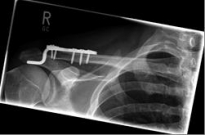

Acromioclavicular (lateral clavicular fracture), should be treated surgically, as a conservative therapy often leads to the formation of a so-called pseudarthrosis. Various implants are available, such as the hook plate and an anatomically preformed angular stable lateral clavicle plate.

Images: A lateral clavicle fracture was treated with a hook plate. The hook is fixed under the acromioclavicular, while screws anchor the plate in the collarbone.